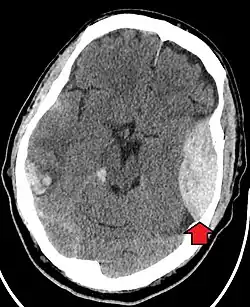

Blunt cranial trauma

The primary clinical concern with blunt trauma to the head is damage to the brain, although other structures, including the skull, face, orbits, and neck are also at risk.[8] Following assessment of the patient's airway, circulation, and breathing, a cervical collar may be placed if there is suspicion of trauma to the neck. Evaluation of blunt trauma to the head continues with the secondary survey for evidence of cranial trauma, including bruises, contusions, lacerations, and abrasions. In addition to noting external injury, a comprehensive neurologic exam is typically performed to assess for damage to the brain. Depending on the mechanism of injury and examination, a CT scan of the skull and brain may be ordered. This is typically done to assess for blood within the skull or fracture of the skull bones.[17]

Traumatic brain injury (TBI) is a significant cause of morbidity and mortality and is most commonly caused by falls, motor vehicle crashes, sports- and work-related injuries, and assaults. It is the most common cause of death in patients under the age of 25. TBI is graded from mild to severe, with greater severity correlating with increased morbidity and mortality.[17][18]

Most patients with more severe traumatic brain injury have a combination of intracranial injuries, which can include diffuse axonal injury, cerebral contusions, and intracranial bleeding, including subarachnoid hemorrhage, subdural hematoma, epidural hematoma, and intraparenchymal hemorrhage.[8][17] The recovery of brain function following a traumatic injury is highly variable and depends upon the specific intracranial injuries that occur. However, there is a significant correlation between the severity of the initial insult as well as the level of neurologic function during the initial assessment and the level of lasting neurologic deficits.[17] Initial treatment may be targeted at reducing the intracranial pressure if there is concern for swelling or bleeding within the skull. This may require surgery, such as a hemicraniectomy, in which part of the skull is removed.[8][17]